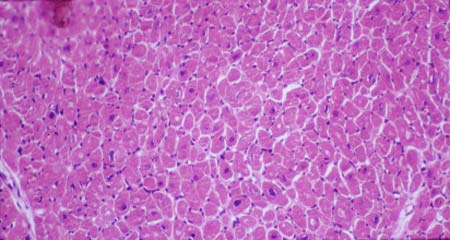

V-62G Cross-section of cardiac muscle.